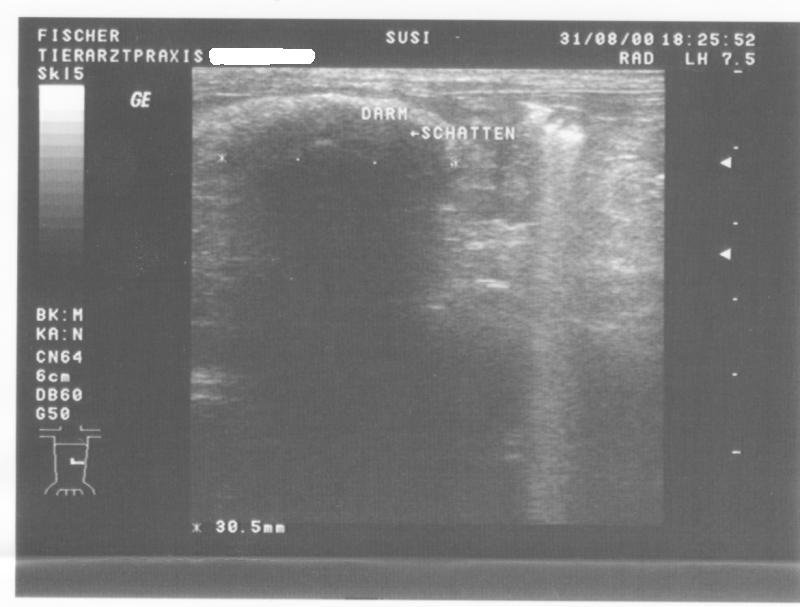

Ultarschall1 Ultarschall2 zurueck